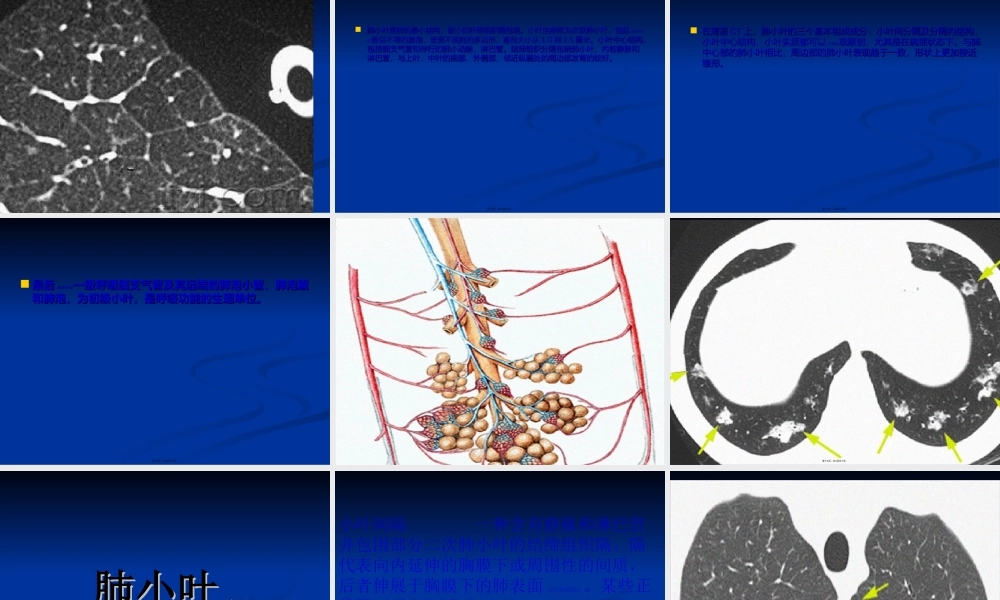

胸部胸部(xiōnɡbù)(xiōnɡbù)影像征象图影像征象图解解lihongdelihongde第一页,共三百五十页。有关(yǒuguān)正常解剖的术语第二页,共三百五十页。.肺实质(.肺实质(lungparenchymalungparenchyma):指肺内各级):指肺内各级(ɡèjí)(ɡèjí)支气管及其终端的肺泡结构,即与肺内支气管及其终端的肺泡结构,即与肺内空气接触的腔隙和管壁。由气管、主支气管、叶支气管、段支气管、小支空气接触的腔隙和管壁。由气管、主支气管、叶支气管、段支气管、小支气管、细支气管、终末细支气管、呼吸性细支气管、肺泡管、肺泡囊和肺气管、细支气管、终末细支气管、呼吸性细支气管、肺泡管、肺泡囊和肺泡等泡等2323级组成。级组成。第三页,共三百五十页。..肺间质(肺间质(lunginterstitiumlunginterstitium):指肺泡间隔、空气腔隙周围及):指肺泡间隔、空气腔隙周围及支气管血管周围的间质,由结缔组织支气管血管周围的间质,由结缔组织(jiédì-zǔzhī)(jiédì-zǔzhī)及其中的血管、淋及其中的血管、淋巴管、神经组成。巴管、神经组成。第四页,共三百五十页。上呼吸道上呼吸道(shànghūxīdào)(shànghūxīdào)((upperrespiratoryairwayupperrespiratoryairway):即鼻、):即鼻、咽和喉。咽和喉。第五页,共三百五十页。下呼吸道(下呼吸道(lowerrespiratoryairwaylowerrespiratoryairway):包括):包括(bāokuò)(bāokuò)气管和各级支气气管和各级支气管和细支气管。管和细支气管。第六页,共三百五十页。小气小气(xiǎoqi)(xiǎoqi)道(道(smallairwaysmallairway):又称膜性气道):又称膜性气道((membranousairwaymembranousairway),指管径≤),指管径≤2mm2mm的的77~~1616级小支气管和细支气管。级小支气管和细支气管。第七页,共三百五十页。大气道(大气道(largeairwaylargeairway):又称软骨性气):又称软骨性气(xìngqì)(xìngqì)道道((cartilaginousairwaycartilaginousairway),指管径>),指管径>2mm2mm的的00~~66级气级气道,包括气管、主支气管、叶支气管、段支气管和道,包括气管、主支气管、叶支气管、段支气管和55~~66级级小支气管。小支气管。第八页,共三百五十页。传导传导(chuándǎo)(chuándǎo)气道(气道(conductingairwayconductingairway):又称导气部):又称导气部((conductingregionconductingregion),即终末细支气管以上属传导气),即...